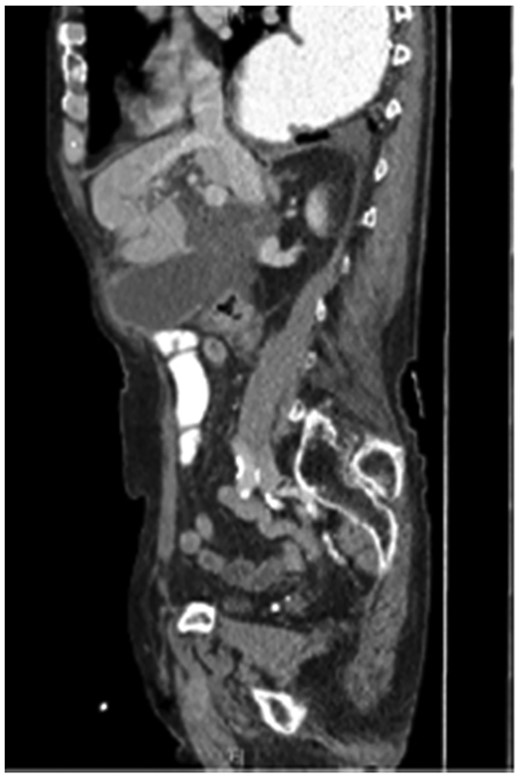

Seventy-six-year-old male with a past medical history of COPD and esophageal cancer status post gastric pull-through procedure 25 years prior, presented to the Emergency Department with a chief complaint of sudden onset epigastric pain that began 24 hours prior while at rest. The pain progressively worsened and radiated to both his right upper quadrant and back with associated chills and nausea/vomiting. He was found to be febrile (38.1C) with a leukocytosis (18.77), hyperbilirubinemia (2.8), transaminitis (418/196) and elevated alkaline phosphatase (168) and lipase (>2250). A CT abdomen/pelvis with IV contrast demonstrated a thickened gallbladder wall, pericholecystic fluid and associated edema of the pancreas consistent with acute cholecystitis and pancreatitis. While the CT showed postoperative changes given his history of esophagectomy with gastric conduit, multiple unique anatomic abnormalities were also noted, including the presence of the gallbladder through a ventral hernia to where it was flush with the skin/subcutaneous tissue of the anterior abdomen (Figs 1 and 2). By hospital day 2, the patient’s lab values were downtrending, consistent with a transient common bile duct stone. Follow-up MRCP confirmed the diagnosis of acute calculous cholecystitis with obstruction of the cystic duct and patency of the common bile and pancreatic ducts. The decision was made to take the patient to the operating room for cholecystectomy with cholangiography. In the operating room, a right subcostal incision was made using electrocautery with a hernia sac encountered directly deep to the subcutaneous tissue. The peritoneum of the hernia was opened and the tip of the gallbladder was immediately encountered. On gross examination, necrosis was noted with evidence of microperforation into the hepatic plate, though no gross contamination was present. The gallbladder was dissected off the hepatic plate, the cystic artery was identified and ligated and stones palpable within the cystic duct were milked retrograde prior to ligation of the cystic duct. The gallbladder was removed and sent for definitive pathologic review. The hernia sac and skin were reapproximated in a multi-layered closure but the fascial edges were not amenable to primary closure secondary to both chronicity and size of the incisional hernia. The patient tolerated the procedure well and was able to discharge home on hospital day 5 (Post-operative day 3). Final pathology was consistent with acute calculous gangrenous cholecystitis. The patient was seen for follow-up 1 month post-operatively and was doing well with no complaints or return of symptoms.

The coronal section of the abdomen/pelvis CT scan illustrating our patient’s incisional hernia containing his gallbladder.